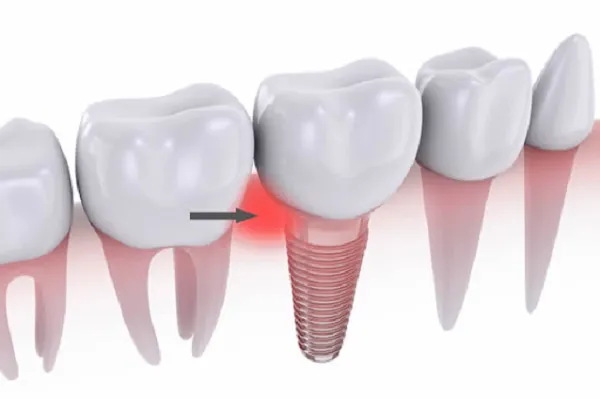

Trồng răng implant là phương pháp được áp dụng để phục hồi răng hiệu quả. Tuy nhiên, vì đây là phương pháp cần tiểu phẫu nên nhiều

Hiện nay, phương pháp trồng răng implant đang được áp dụng phổ biến hiện nay. Đây là phương pháp giúp người mất răng có thể phục hồi

Trồng răng implant Hải Phòng: Giải pháp an toàn cho người bị mất răng Công nghệ trồng răng implant là bước tiến mới trong ngành nha khoa.

Hiện nay, những người mất răng đã có thể tự tin nhờ công nghệ trồng răng implant. Đây là một thành tựu khoa học công nghệ phổ